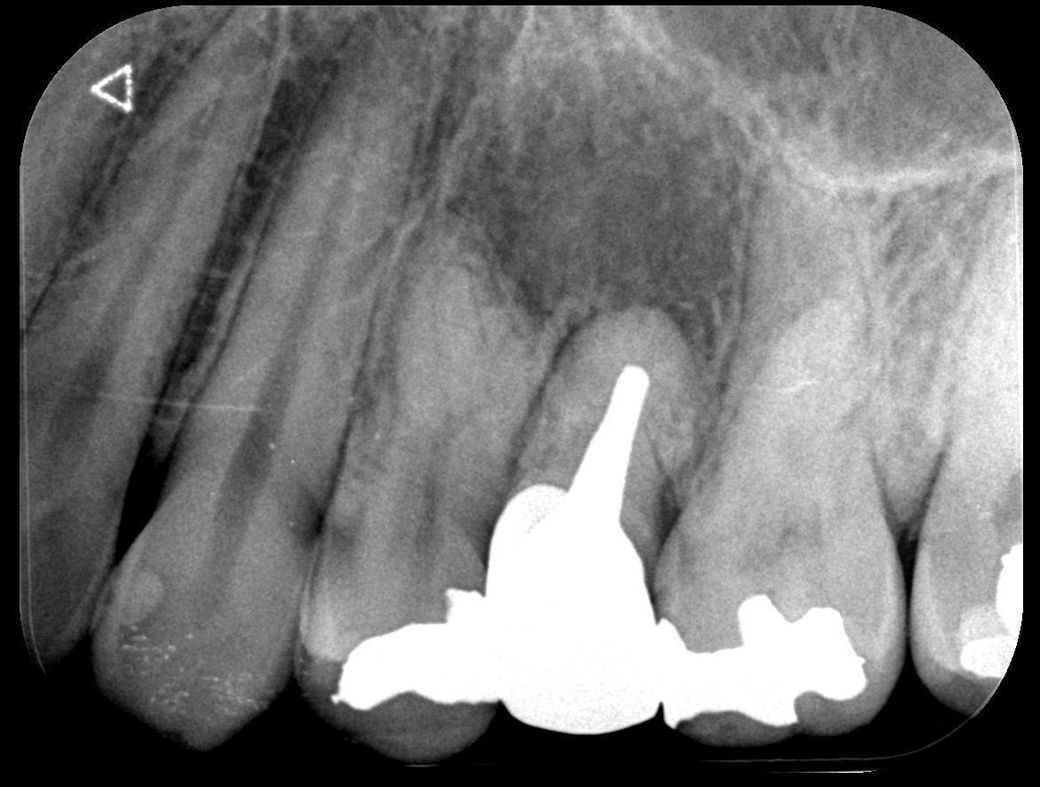

사진 찍고 진료받아보니 뿌리 쪽 잇몸 안에 큰 물혹 염증 같은 게 가득 차 있다고 크기도 많이 크고 상태가 만히 안 좋다 하셔서

이게 크라운 교체 전에는 없었는데 교체 후에 생긴 거 같다고 3년 전 사진이랑 비교해 주시면서알려주셨는데

뿌리의 병수의 크기로 보면 최근에 생긴 것이 아니라 오랜 기간 동안 진행된 것으로 보입니다. 뿌리 끝에 병소가 너무 크다면 신경치료 등으로 해결이 되지 않을 수도 있기 때문에 큰 병원에서의 치료가 필요할 수 있습니다. 자세한 확인을 위해서 치과에서 진료를 받아보세요.

뿌리끝 염증에서 비롯되는 물혹의 가능성이 있어보입니다. 현재로선 완전히 cyst화된 건 아니고 granular tissue 의 상태로 보여집니다.